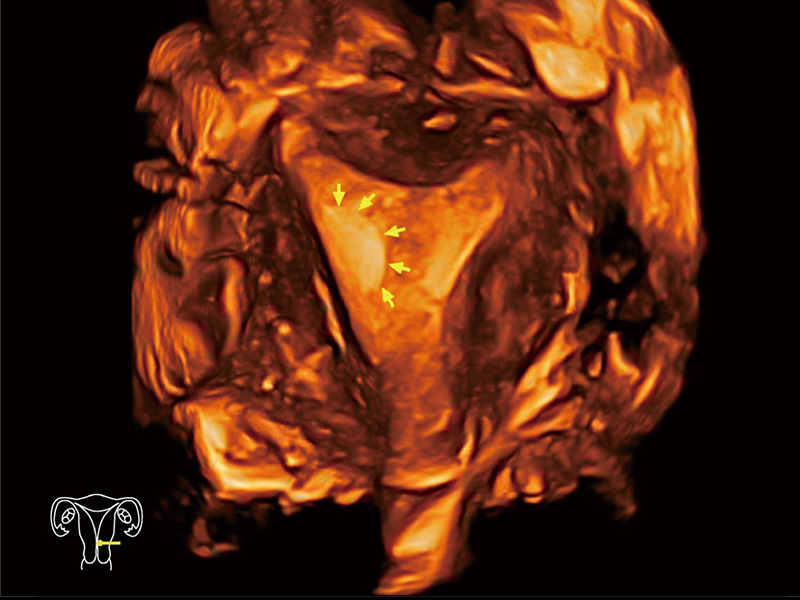

腔内容积探头

腔内三维成像技术获得显著提升,超大扇角在满足日常基础扫查的同时,支持卵泡自动测量及多种三维渲染模式,为您提供更多的诊断信息,尤其是在子宫畸形的诊断,内膜及肿瘤占位观测中起到了重要的作用。

临床图

中央型宫腔粘连